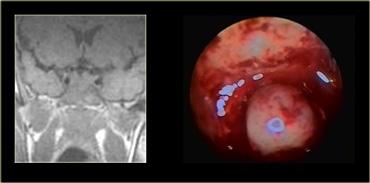

Các hình ảnh này mô tả phẫu thuật cắt bỏ u tuyến yên đại tuyến qua đường xuyên bướm (transsphenoidal resection).

Sau khi phần sàn xương của hố yên được lấy bỏ, màng cứng (dura) được rạch bằng đường rạch hình chữ thập.

Do áp lực phía trên màng cứng lớn hơn áp lực phía dưới, khối u đại tuyến sẽ tự thoát ra vào xoang bướm (sphenoid sinus).

Chụp MRI trong mổ được thực hiện trong một bối cảnh thử nghiệm để xác định xem phẫu thuật viên thần kinh có lấy bỏ thành công toàn bộ khối u hay không.

Do việc sử dụng đường phẫu thuật này có trường nhìn hạn chế, điều quan trọng là phải biết trước mình đang phẫu thuật trên tổn thương gì.

Như chúng ta sẽ thấy, có những tổn thương mà bạn không nên phẫu thuật theo đường tiếp cận này!